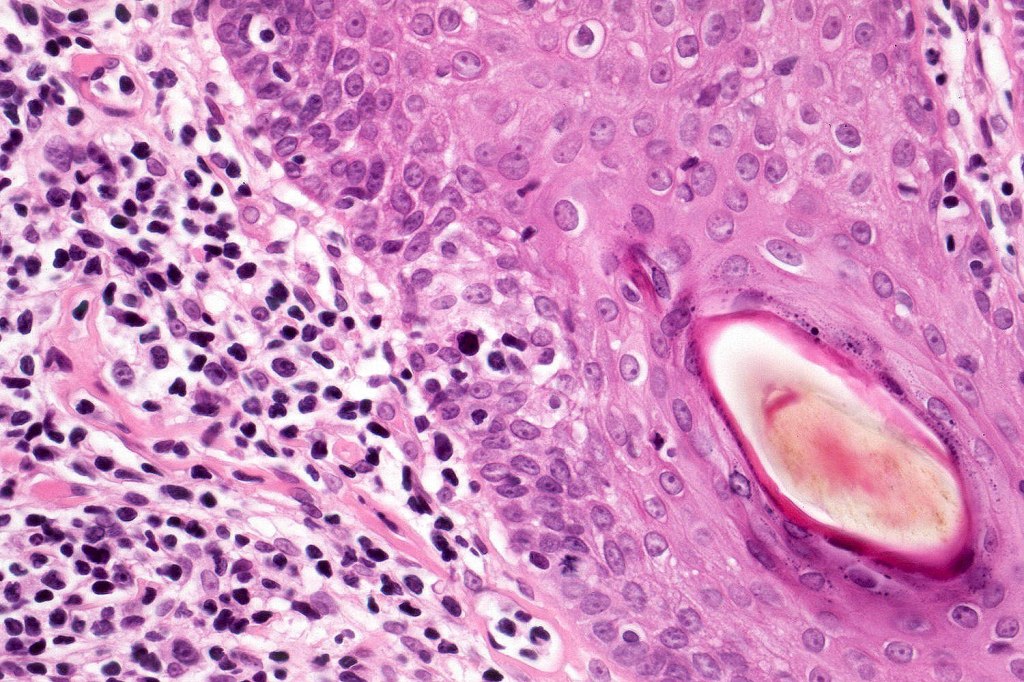

Histological features

•Follicular infiltration by atypical lymphocytes & Sézary cells

•+/- basaloid follicular hyperplasia

•Granulomatous inflammation secondary to follicular destruction